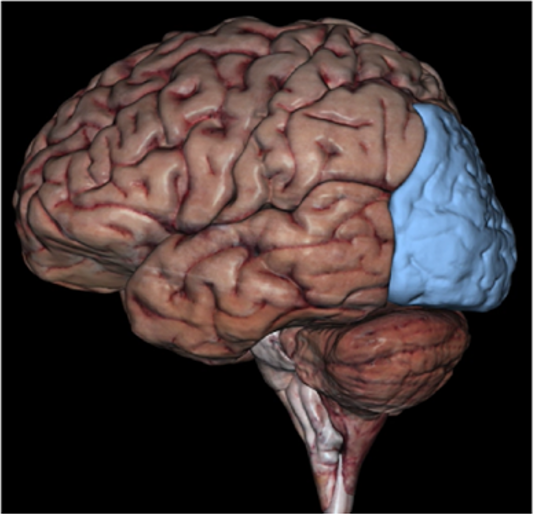

Occipital Lobe

Occipital Lobe